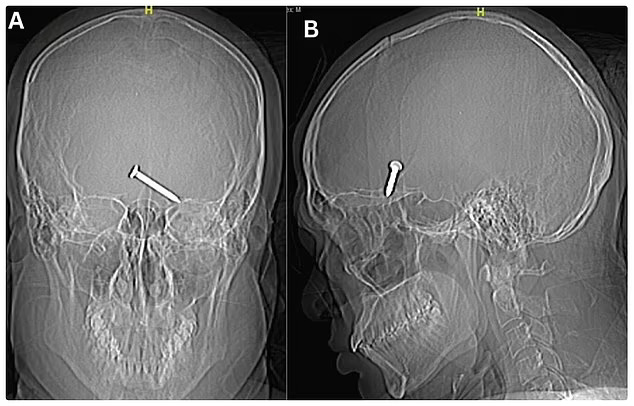

Рендген и КТ скен на неговиот череп покажале дека ноктот навлегол во фронталниот лобус на мозокот – област витална за движење и јазик. Потоа предизвикал крварење, кое се прошири на соседните мозочни региони.